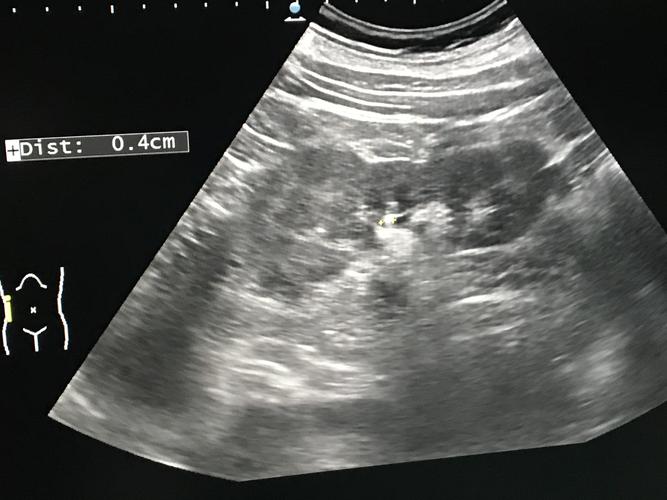

1.3超声右肾结石0.4cm